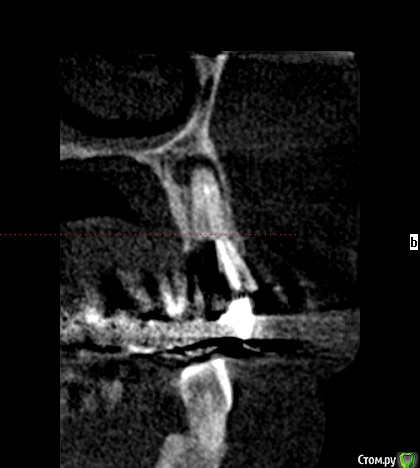

Тимур86 Опубликовано 12 февраля, 2019 Поделиться Опубликовано 12 февраля, 2019 планируется костная пластика 12-22. 23 впоследствии будет удалён,но киста перед нкр смушает...стоит рвк сделать,как думаете? Ссылка на комментарий

Nazim_NV86 Опубликовано 12 февраля, 2019 Поделиться Опубликовано 12 февраля, 2019 Во время НКР и сделайте. +5мин. Крайний правый пин перед очагом. Ссылка на комментарий